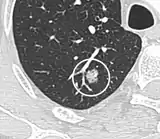

Calcifications and popcorn-like appearance, conferring a diagnosis of hamartoma.[9]

• In case of calcifications, a popcorn-like appearance indicates a hamartoma, which is benign.[3]